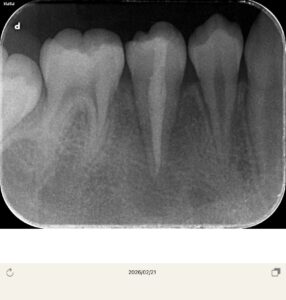

レントゲンは以前のもの

以前冷たいものが染みるということでレントゲンを撮影したが、中心結節が欠けたためと診断し、経過観察を行なっていた。

ところが7ヶ月経過して急に歯茎が腫れてきたとのことで来院

ここの真ん中の歯に中心結節があったが、そこの破折からの根管内への細菌感染とすぐに判断した。CBCTを撮影させていただき、歯根は完成しているため、再生歯内療法(REP)ではなく、MTAで根管充填をしようと計画